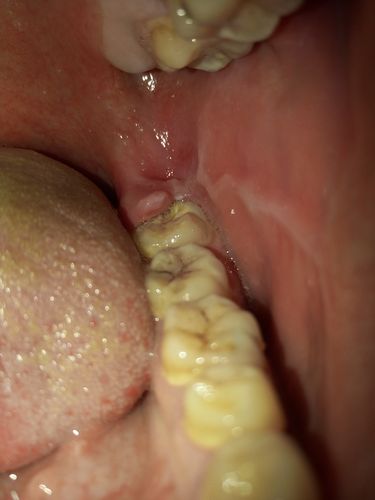

智齿包肉里怎么办图片

智齿包肉里怎么办图片,智齿包在肉里面图片

左右两侧 最里面牙龈有点 微疼.左侧浮肿一点.第七个牙齿酸疼.

智齿包在肉里面图片

肉包智齿图片

智齿半包在肉里面图片

智齿后面的肉肿了图片

牙齿被肉包住了图片

智齿长出一半被肉包着

智齿露一半包一半图